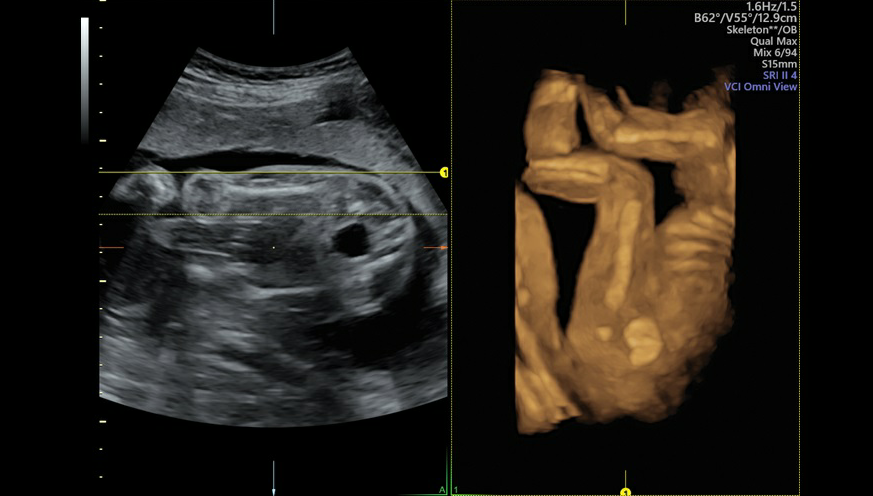

GE VOLUSON E8是目前世界上先进的彩色超声设备,被誉为“神奇彩超”,是筛查胎儿畸形的尖端设备。它提供了包括腹部、血管、小器官、产科、妇科、泌尿科、新生儿和儿科等多领域的多方面的应用。能够显示未出生的宝宝的实时动态活动图像,或者其它人体内脏器官的实时活动图像。通过四维彩超,孕妈妈躺在床上,就可以通过对面的显示屏直接和宝宝见面,还可以看到宫内胎儿,如打哈欠、伸懒腰、吮手指等等奇妙的动作。

Voluson E8的3D/4D容积超声技术已经得到了世界范围的广泛认可,Voluson E8除了保持Voluson产品在3D/4D的成像技术优势以外,在2D图像质量,彩色灵敏度方面有很大提高外,在核心技术如探头、波束形成器、成像模式、人机工程方面,均有了革命性的提高。该系统满足了临床超声医学专家在图像质量、人机工程、工作流程、腔内探头等几个方面提出的期待和希望。